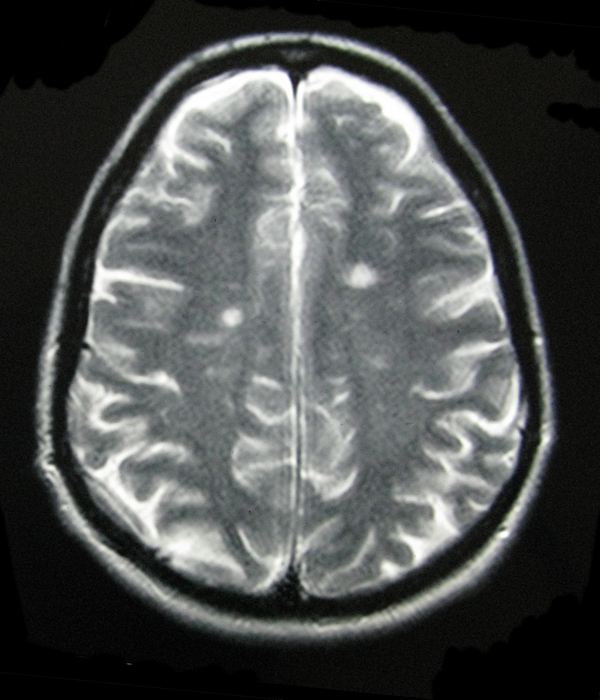

- My Brain in 2009